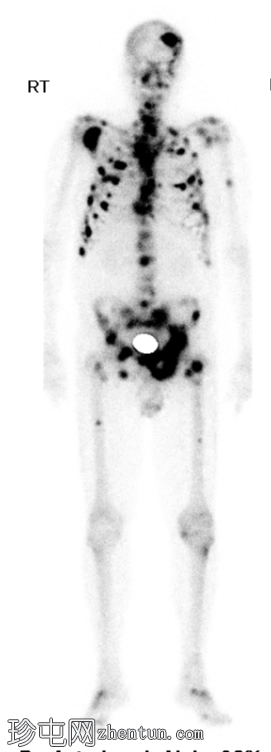

全身

4.jpg

后位

脊柱、肋骨、骨盆、颅骨、肩胛骨、胸骨、左侧肱骨和双侧股骨干可见多处放射性示踪剂摄取异常增高,与SPECT-CT扫描图像上显示的硬化病灶相对应。双肾未见放射性示踪剂活性。

骨骼内多处局灶性放射性示踪剂摄取增高,符合骨转移;肾脏内无放射性示踪剂活性,与超扫描结果一致。